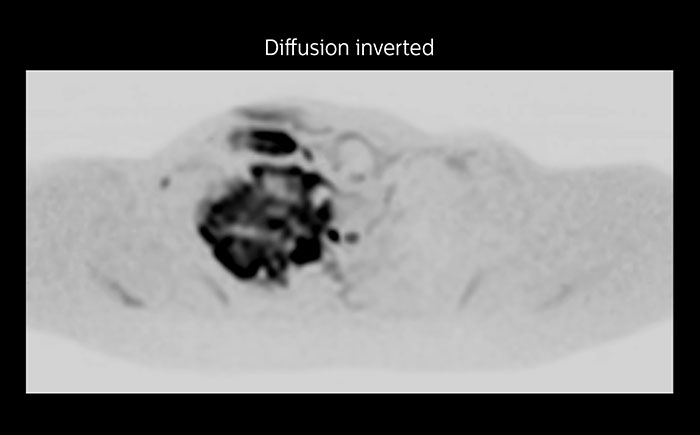

MRI of Pancoast tumor

Although the area between the neck and the top of the lung is one of the most difficult areas for MRI, Prodiva 1.5T images show good quality in this 56-year-old male with Pancoast tumor on the right. mDIXON TFE images shows excellent fat suppression in the neck area and the DWI shows almost no distortion.

Prodiva MRI pancoast tumor DWI, Seirei Mikatahara

Prodiva MRI pancoast tumor mDixon, Seirei Mikatahara

Prodiva MRI pancoast tumor dynamic, Seirei Mikatahara